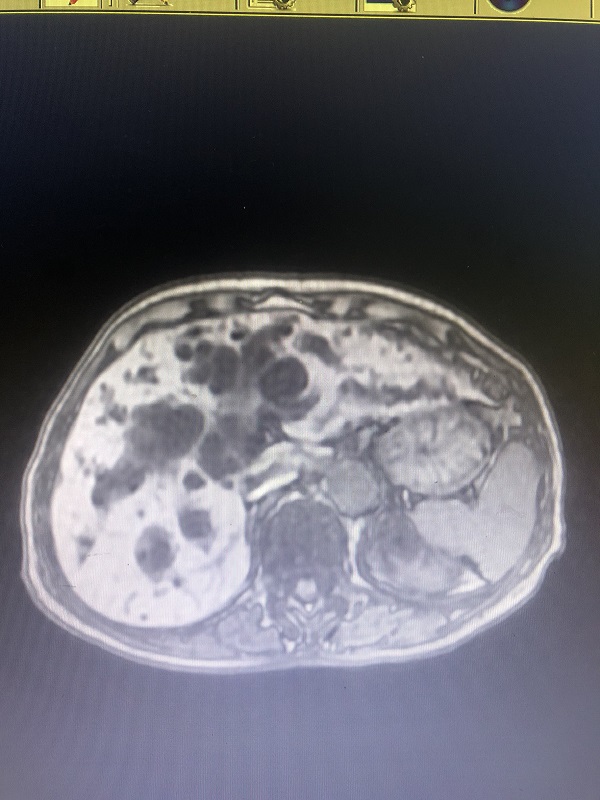

患者袁某是一名86岁的女性,因“无痛性黄疸20余天”入院。辅助检查,肝功能示:黄疸极为严重,低蛋白血症;上腹部MRI+MRCP示:肝门区占位性病变并肝内胆管扩张,胆管细胞癌可能;MRCP:肝内胆管明显扩张。